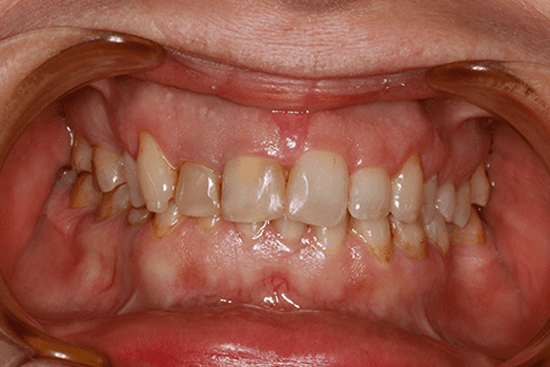

Gummy smile” – wysoka dynamika uśmiechu z nadmierną ekspozycją dziąseł. Szkliwo zębów zniszczone z dużymi przebarwieniami. Braki zębowe w łuku dolnym.

Pacjentka marzyła o uśmiechu jakiego nigdy nie miała. Istotne było także uzupełnienie braków zębowych.

Po przeprowadzonym badaniu oraz wykonaniu cyfrowego projektu uśmiechu, pacjentka przeszła kilka nieinwazyjnych procedur estetycznych polegających na korekcie kształt dziąsła. Następnie doktor Markiewicz wraz z zespołem protetycznym wykonał cienkościenne licówki E-max korygujące zarówno wysoki uśmiech dziąsłowy, jak i kształt oraz kolor zębów. Braki zębowe zostały uzupełnione przy zastosowaniu implantów stomatologicznych.